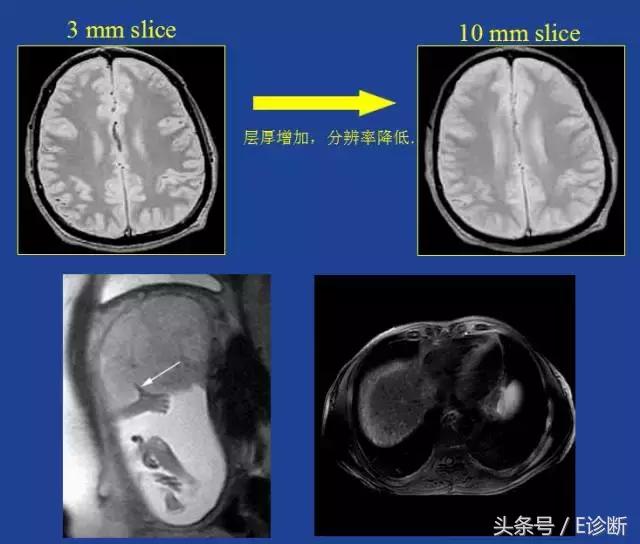

部分容积伪影

原因:

由于像素过大,导致像素内信号平均,使一个体素内混合多种组织对比,分辨率降低。

伪影特点:

同一像素中显示多种组织,易对临床诊断造成混淆

解决办法:

降低层厚

截断伪影

原因: 有限的采样次数和采样时间不能准确描述一个阶梯状信号的强度变化。

伪影特点: 相位方向更常见,在高对比度界面(颅骨/脑、脊髓/CSF、半月板/液体等)形成交替的亮带和暗带。